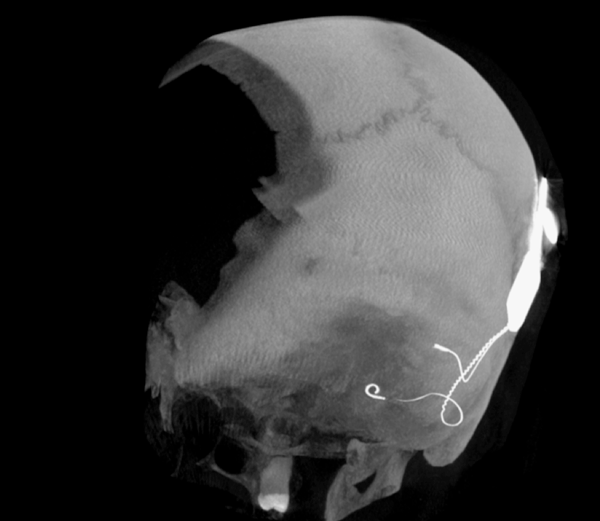

Both patients were imaged immediately with CBCT using SCANORA® 3Dx (Soredex, Tuusula, Finland). The field of view (FOV) was 140 x 165 mm and voxel size 0.2 mm. Imaging parameters were 90 kV, 8 mA, 4.00s. Standard 1 mm axial, coronal and sagittal reformations were made, as well as MIP and 3D reconstructions using OnDemand3D™ software (Cybermed, Seoul, South Korea).

CBCT proved to be optimal for imaging of these implants because of the superior bony delineation and nearly artefact free images. All four parts, i.e. the receiver stimulation part, extracochlear electrode implanted on the surface of the temporal bone, the extracochlear electrode plate and the intracochlear electrode array could be well imaged with CBCT.

On CBCT all four of the important parts of the implant were very well seen both on the axial slices and three dimensional surface reconstruction images. The implant is placed on magnetic plates, and the extracochlear part was seen in an abnormal separated position. The intracochlear electrode array showed no signs of separation in either of the cases. The intracochlear electrodes were well seen in both of the cases.

Figure 4: 3D MIP image of patient 2.